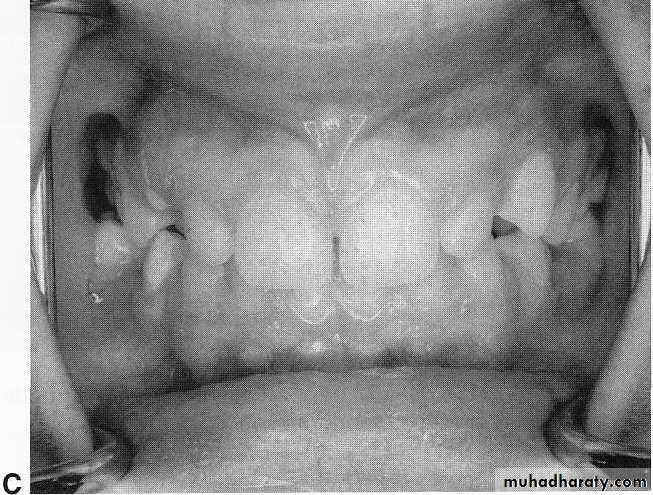

A, Prepubertal periodontitis in a 41/2-year-old girl. Loosening, migration, and spontaneous loss of the primary teeth occurred.

C, Eight years after the initial observation of an involvement of the supporting tissues, there is evidence of normal gingival tissues. It is believed that dietary counseling and excellent oral hygiene contributed to the success of the treatment.